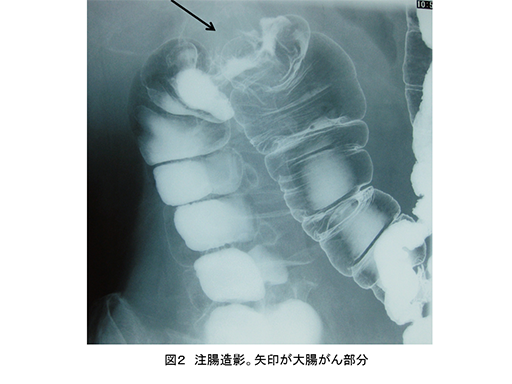

進行がんでは右側結腸(盲腸~横行結腸)と、左側結腸(下行結腸~S状結腸)・直腸とで症状が異なります(図1、図2)。

注腸造影。矢印が大腸がん部分